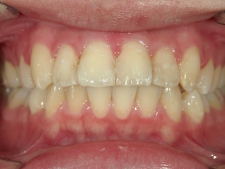

矯正歯科 治療後矯正歯科 プチワイヤー矯正 治療後矯正歯科(プチワイヤー矯正)治療後

矯正歯科 治療後

no.6_8296_治療後_右.jpgno.6_8296_治療後_正面.jpgno.6_8296_治療後_左.jpg